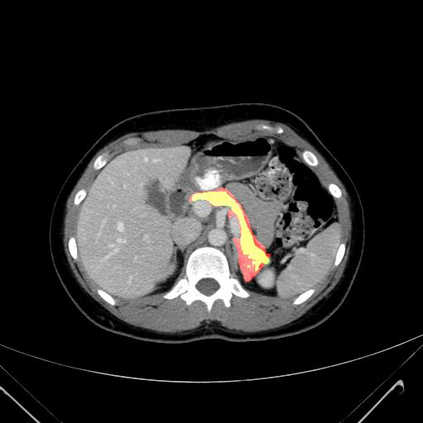

In this paper, we adopt 3D Convolutional Neural Networks to segment volumetric medical images. Although deep neural networks have been proven to be very effective on many 2D vision tasks, it is still challenging to apply them to 3D tasks due to the limited amount of annotated 3D data and limited computational resources. We propose a novel 3D-based coarse-to-fine framework to effectively and efficiently tackle these challenges. The proposed 3D-based framework outperforms the 2D counterpart to a large margin since it can leverage the rich spatial infor- mation along all three axes. We conduct experiments on two datasets which include healthy and pathological pancreases respectively, and achieve the current state-of-the-art in terms of Dice-S{\o}rensen Coefficient (DSC). On the NIH pancreas segmentation dataset, we outperform the previous best by an average of over 2%, and the worst case is improved by 7% to reach almost 70%, which indicates the reliability of our framework in clinical applications.